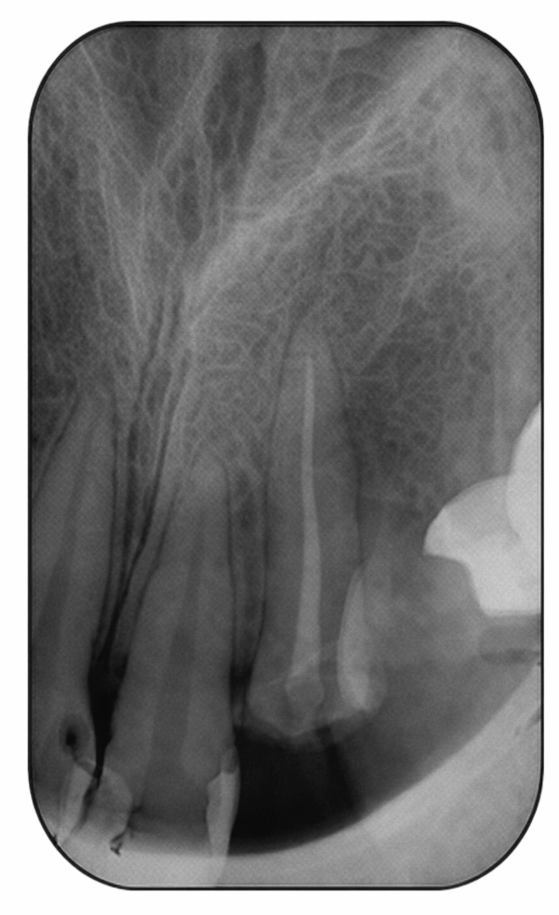

- La radiographie préopératoire :

Elle renseigne sur la morphologie canalaire et permet de déterminer la longueur du logement du tenon et son diamètre, ainsi que la qualité de l’obturation canalaire. - Le champ opératoire :

1-La radiographie préopératoire :

Elle nous renseigne sur la morphologie canalaire et permet de déterminer la longueur du logement du tenon et son diamètre, ainsi que la qualité de l’obturation canalaire.